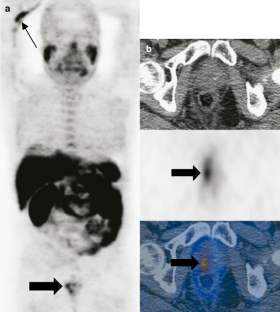

Fig. 1

Fig. 2

Fig. 3

Fig. 4

Fig. 5